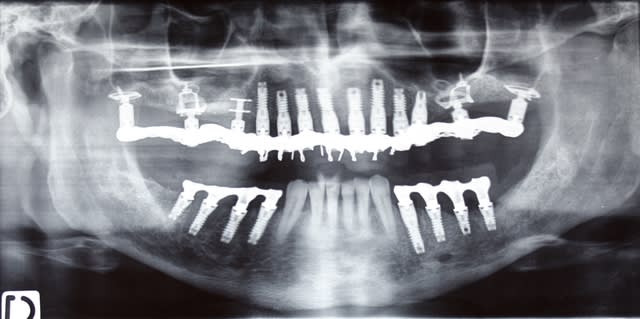

un image serait la bienvenue!